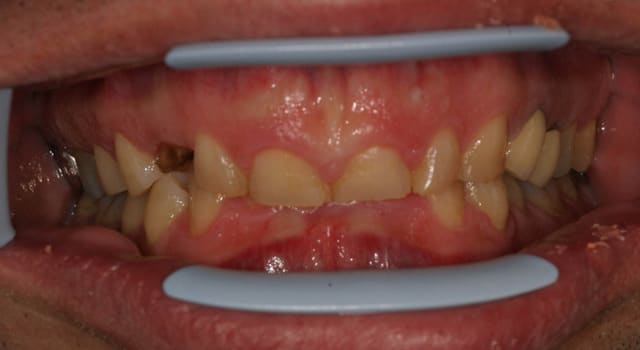

ce patient, 40 ans, non fumeur, sans de pb de santé particulier consulte pour un problème esthétique sur la 53. il est aussi inquiété par l'usure de ses incisives.

l'abrasion des incisives, l'éggression des groupes incisivo-canin maxillaire et mandibulaire pour compenser cette abrasion, et l'occlusion me laissent dubitatif.

J'avais envisagé dans un premier temps de proposer de l'ortho pour lever la supracclusion et permettre la pose d'un implant pour remplacer la 13, et reconstituer les incisives, mais l'absence d'une veritable perte de DV me laisse un peu sec pour le plan de traitement. Toutes les idées sont les bienvenues.

Sur les modèles seul les incisives et canines sont abrasées. Les molaires et PM ne montrent aucunes facettes d'usure.